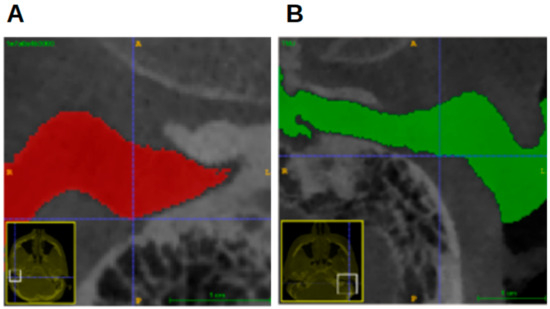

Per individual, five landmarks were established in the left and right external acoustic meatus: the most anterior point (MAP); the most posterior point (MPP); the most superior point (MSP); the most inferior point (MIP); and the notch-like rim between the innermost portion of the EAM and the epitympanic recess. As this has no official name, it is referred to as the epitympanic notch (EN) (Figure 2). Angular structures were sought because they might be easier to reproduce [16].

Figure 4 shows the most anterior and the most posterior point, marked with a white circle and a pink circle, respectively. Figure 5 shows the most superior and the most inferior point, marked with a blue circle and a yellow circle, respectively. In Figure 2, the EN is indicated by a red arrow.

Figure 2. The location of the epitympanic notch. (A) A CBCT image of a right acoustic meatus in a coronal view. The red arrow indicates the epitympanic notch. (B) A cross-section through the external acoustic meatus (“MedicalGraphics–Drawing Ear anatomy–no labels” at AnatomyTOOL.org by www.MedicalGraphics.de; license: Creative Commons Attribution-NoDerivatives).